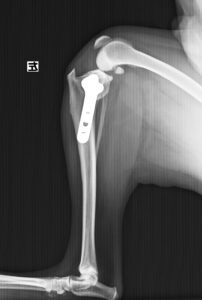

ジャンプした拍子に右後肢跛行とのことでかかりつけ医を受診後、セカンドオピニオンとして当院の整形外科に来院されました。若い雄猫に多く見られる「大腿骨頭すべり症」と診断。ご家族様と相談の上、骨頭切除を実施しました。経過は順調でしたが、その6ヶ月後に逆側も同様に骨折し、同治療を行いました。結果的に両側の骨頭切除が行われましたが、経過は良好です。